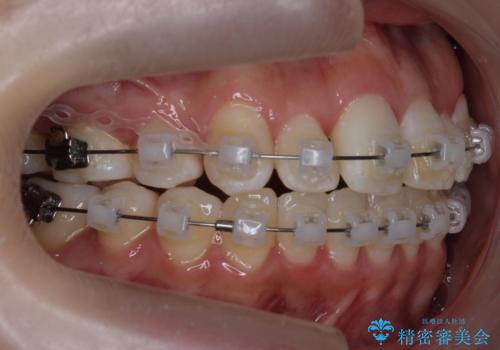

前歯は重度のがたつき、また奥歯はすれ違っていました。

治療は3年以上かかりそうと説明しましたが、2年台で終わらせることができました。

上下左右4本抜歯の可能性を説明していましたが、実際は上顎2本の小臼歯抜歯で済みました。

矯正用インプラントを使用して治療しています。